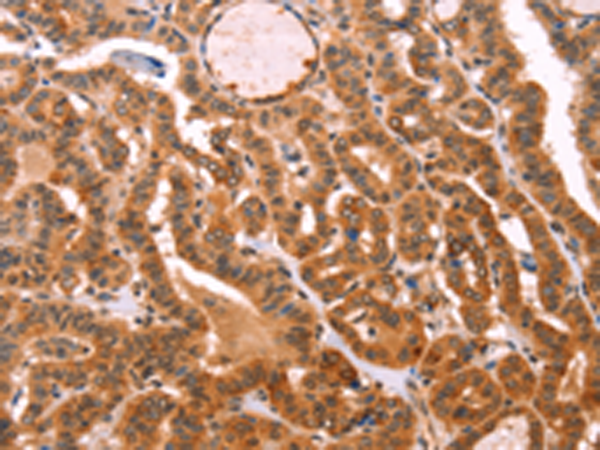

分类: 科研抗体货号: P07698别名: CMM8; OCA1A; OCAIA; SHEP3应用: WB,IHC反应种属: Human, Mouse